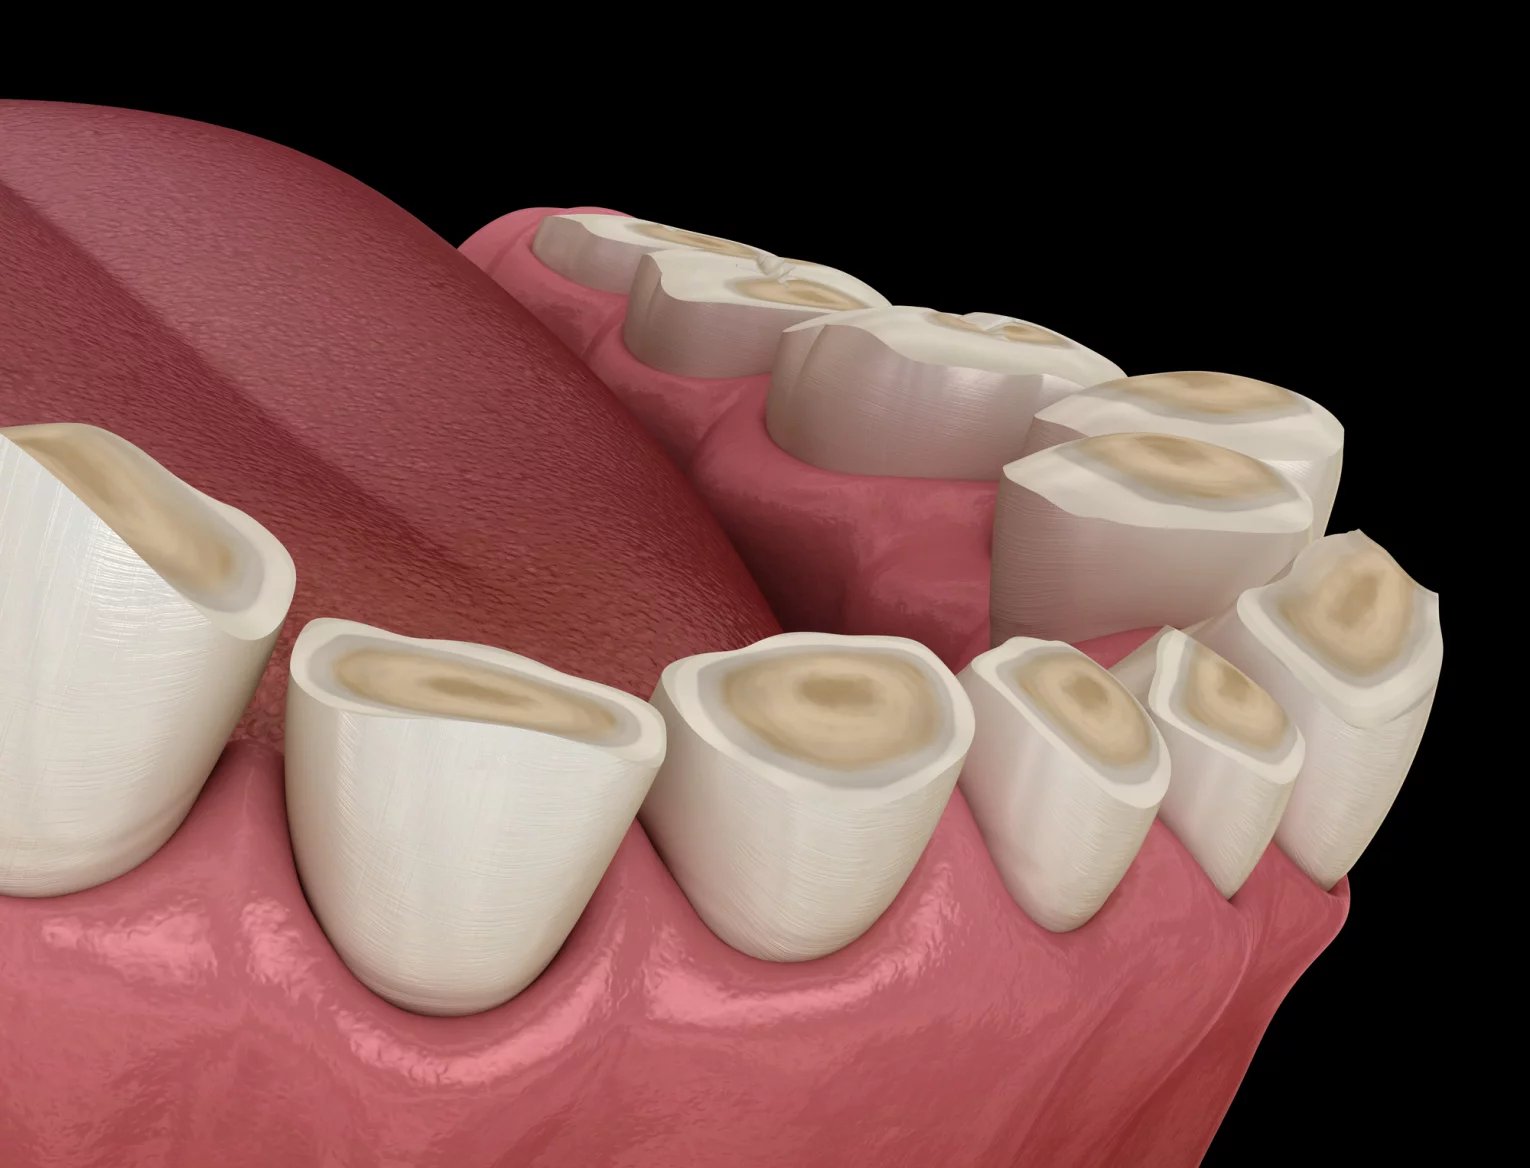

Nevědomé skřípání či zatínání zubů zvané bruxismus pacienty postihuje ve dne, ale nezřídka i při nočním spánku. Může souviset se stresem, celkovým držením těla, spánkovou apnoe, pitím alkoholu i kofeinu, kouřením, užíváním některých léků a mnoha dalšími faktory, z nichž některé jsou dosud neodhalené.

Stanoví-li stomatolog tuto diagnózu, není radno nad ní mávnout rukou. Bruxismus může způsobovat bolesti hlavy, žvýkacích svalů, čelistního kloubu nebo poškození zubů nebo protetiky. Noční skřípání zuby může obtěžovat osoby, se kterými pacient sdílí ložnici,

Předejít poškození zubů může třeba speciální dlaha, zpravidla nasazovaná na dolní zuby. Jenže ta neodstraní samotné skřípání, jen při vložení do úst nedopustí, aby se při něm poškozovala sklovina.